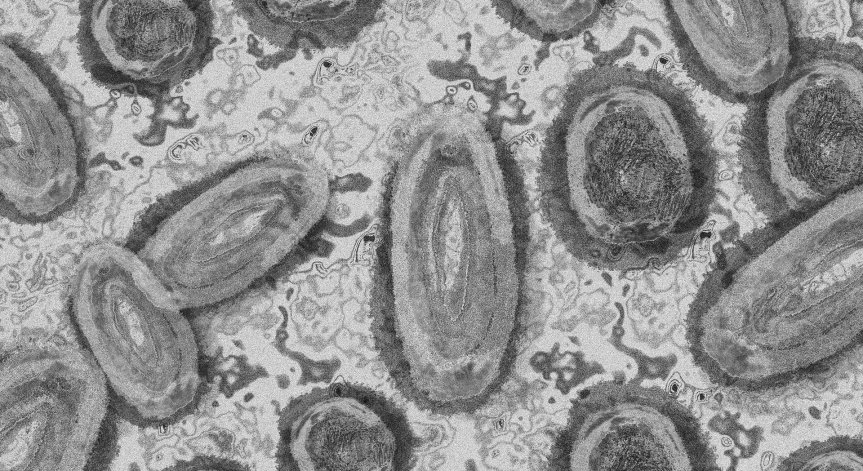

Вирусът се предава при близък контакт. Голям процент от заразените са хомосексуалисти. Маймунската шарка може да се разпространи и при докосване на дрехи, спално бельо, използвани от заразен или при кашляне и кихане.